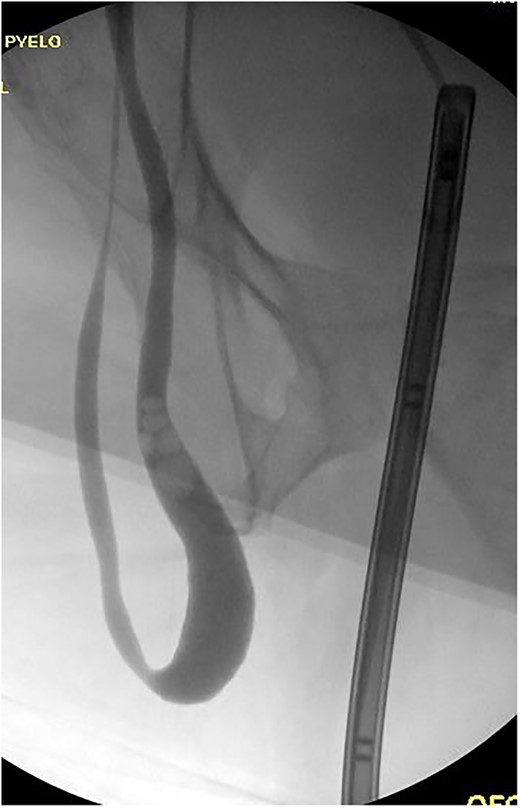

This is a 60-year-old male with a body mass index of 45.4 who was referred to the emergency room with a complaint of acute onset left flank pain. Past medical history was significant for hypertension and hyperlipidemia. Past surgical history was notable for appendectomy and multiple right lower extremity operations as a child to correct deformities from polio. He continued to require right lower extremity bracing. At the time of diagnosis, he had no additional gastrointestinal or urinary symptoms. Examination was notable for bilateral groin bulge suggestive of hernia versus hydrocele. The complete blood count, basic metabolic panel and urinalysis were unremarkable. A computerized tomography (CT) scan of the abdomen was performed and revealed bilateral inguinal hernias containing ureters and fatty tissue (Fig. 1). Mild right hydronephrosis was noted. Pain improved after the administration of ketorolac and patient was referred to general surgery for further evaluation.

CT Urogram with bilateral ureteroinguinal scrotal hernia. Maximum intensity projection image has been reformatted to highlight both ureters crossing the inguinal canals.